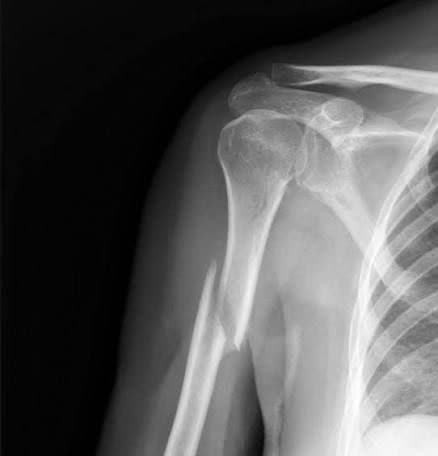

برای اولین بار در بیمارستان فاطمیه بادرود جراحی درمان شکستگی بازو با استفاده از پیچ و پلاک با موفقیت انجام شد.

این جراحی بزرگ و تخصصی و حساس توسط  پزشکان معالج جناب آقای دکتر حمیدرضا حاجی هاشمی، متخصص جراح ارتوپدی و سرکار خانم دکتر لیلی مهرزاد متخصص بیهوشی و مراقبت‌های ویژه انجام گرفت. جراحی فوق با همراهی و همکاری بی‌نقص کارکنان اتاق عمل انجام شد.